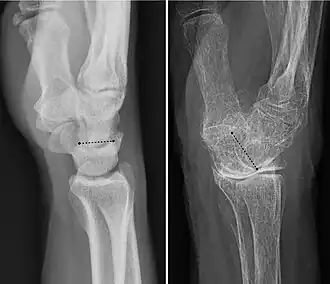

Projectional radiograph of a normal wrist (left image) and one with a dorsal tilt due to wrist osteoarthritis (as well as osteoporosis). The angle of the distal surface of the lunate bone is annotated. A dorsal tilt of 10 to 15 degrees is considered normal.[18]